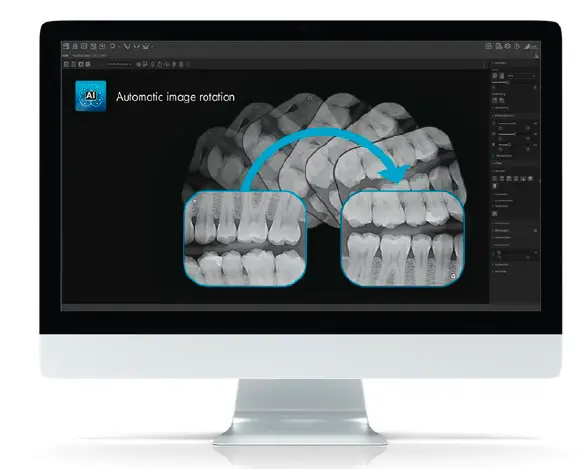

Automatic image rotation

VistaSoft uses an algorithm based on artificial intelligence to check the orientation of intraoral X-ray images using the anatomical features shown and corrects the rotation of the image automatically if needed. This will save you valuable time.